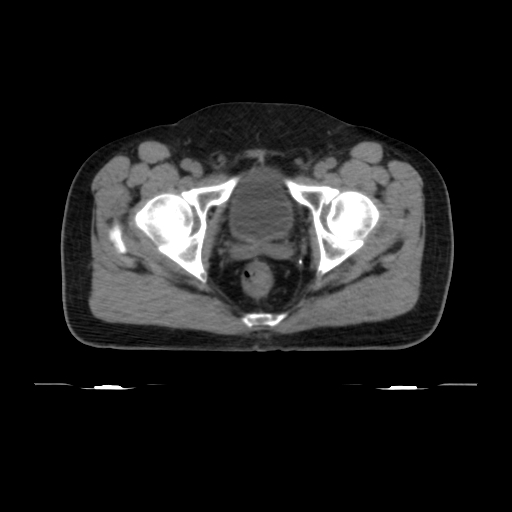

ClearRT® Images

Imaging Information

ClearRT®

Protocol

Pelvis-normal-FOV50cm

Scan Length

9 cm

KVCT Imaging Time

18 sec